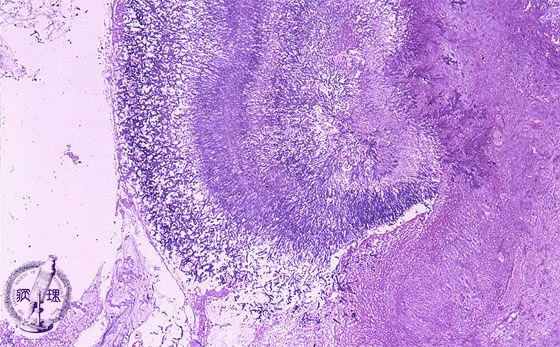

Microscopic view (HE stain, low power view): Hematoxylin stained aspergillus hyphae are septate, 3-11um in diameter and demonstrate Y-shaped branching at a roughly 45 degree angle, characteristics which help differentiate from other fungi.